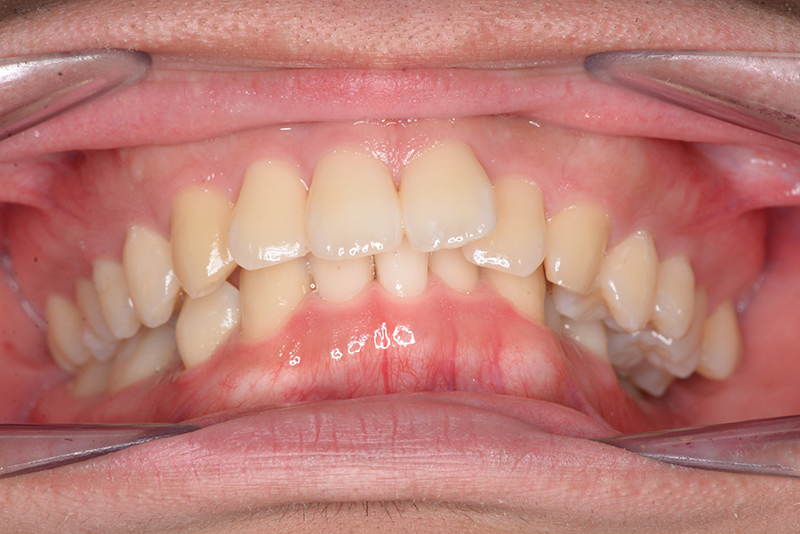

主訴 物が噛みづらい 診断名 下顎右側側切歯先天欠如を伴う過蓋咬合症例

口腔内所見 over jet 8.5mm、over bite 6.0mm、下顎前歯先天欠如、右側臼歯関係I級、左側II級(end on)、上顎歯列弓はオーボイド型なのに対して、下顎は狭窄歯列、叢生歯列弓を呈しており左側は鋏状咬合となっていた。